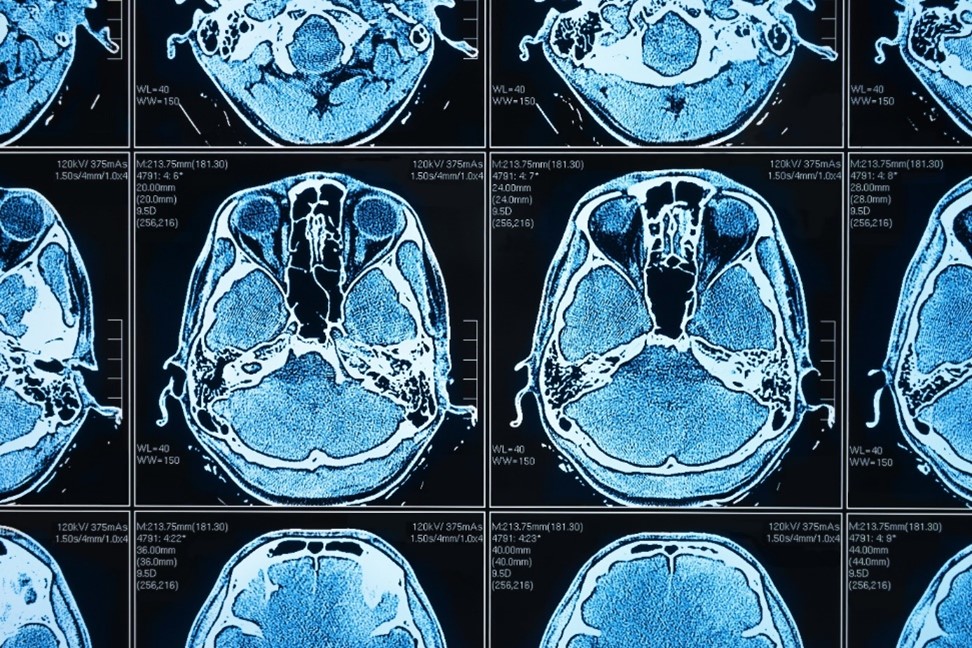

Künstliche Intelligenz (KI) und darauf gestützte Anwendungen werden in der medizinischen Praxis immer wichtiger. Und sie bieten unschlagbare Vorteile, beispielsweise in der Bildanalyse: Big-Data-Auswertungen und Massenverarbeitung von computergenerierten Dateien, Abgleich zwischen verschiedenen Datenbanken, Erkennung von Mustern und – fast noch wichtiger – von Abweichungen, Betrachtung von Entwicklungen im zeitlichen Verlauf, … die Liste der Anwendungsmöglichkeiten ist lang. Denn bei all diesen Aufgaben kann KI um ein Vielfaches effektiver und zuverlässiger „agieren“ als der Mensch.

Künstliche Intelligenz stellt eine ideale Ergänzung bei all jenen Aufgaben dar, die hohe Präzision und Effizienz erfordern. Gerade im Gesundheitswesen und insbesondere bei der Auswertung von bildgebenden Verfahren finden sich hier praktische Anwendungsszenarien en masse. Zudem ist künstliche Intelligenz bekanntlich trainierbar: Machine-Learning-Modelle erlauben es, große Datenvolumina in KI-Anwendungen einzuspeisen und diese entsprechend anzulernen, um zum gewünschten Abstraktionsniveau und damit zu belastbaren Ergebnissen zu kommen. Mit jedem neuen Datensatz wird die KI praktisch intelligenter und damit genauer.

Damit KI erfolgreich eingesetzt werden kann, braucht es umfangreiche und heterogene Trainingsdaten. Ein zuverlässiges Krebserkennungsmodell sollte beispielsweise auf der Grundlage von Tausenden von medizinischen Bildern trainiert werden, die gesundes Gewebe und Tumore im Vergleich aufzeigen können. Zugleich sollte das Modell auch die reale Bandbreite von Geschlecht, Alter und anderen demografischen Merkmalen der Patient*innen repräsentieren. Auch müssen visuelle Merkmale, die sich aus den verschiedenen Bildgebungstechniken ergeben, dargestellt werden.